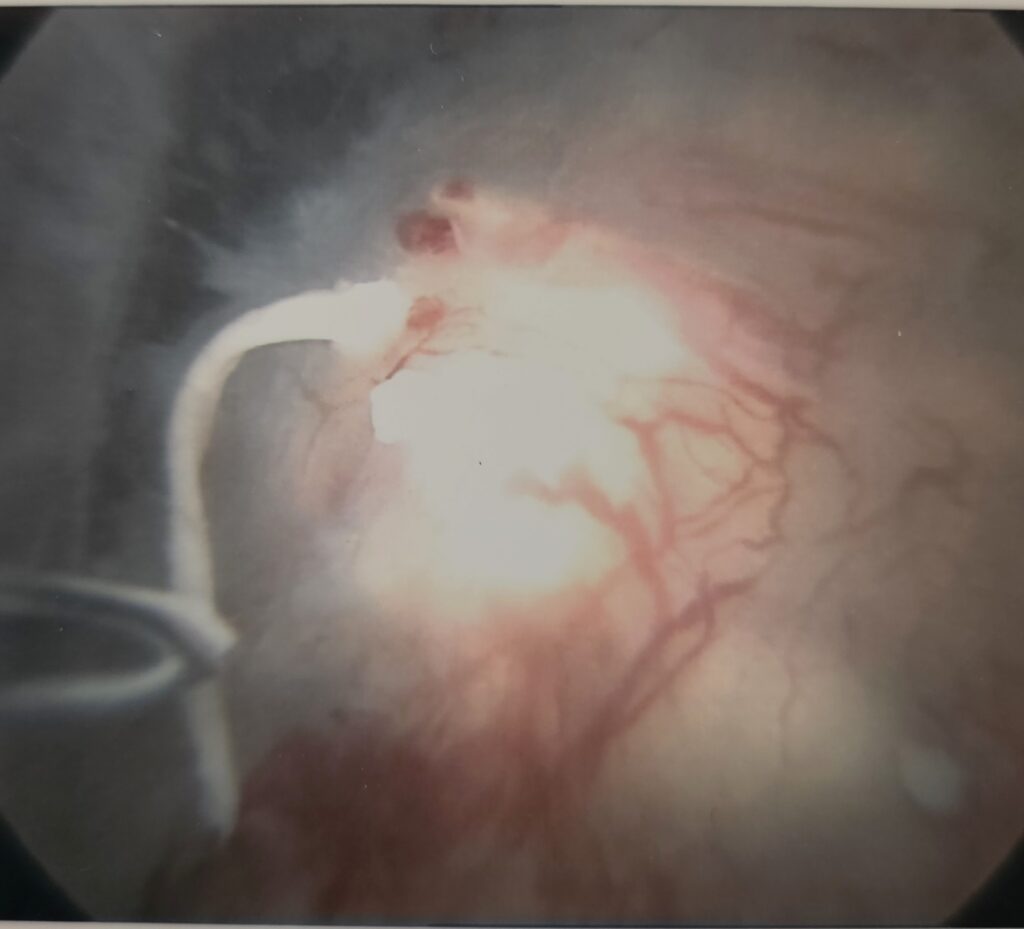

One common problem is a tear of the capsule where it adheres to the shoulderblade part of the joint. This is called a Bankart lesion and can be to the front or the back of the joint. Repair is done arthroscopically using anchors. The outcome of this method is usually very good. Recovery takes about six weeks with the physio being continuously involved.

Above are pictures showing the placement of a suture through the edge of the capsule (labrum) to the placement of the anchor as well as the end result. All of this happens through two small incisions.